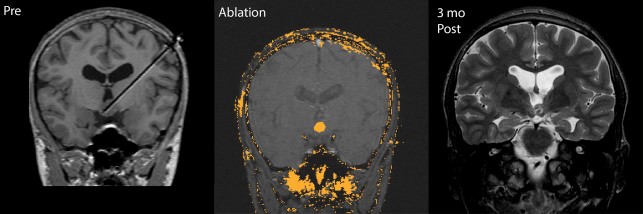

激光间质热疗(LITT)

热/激光消融是一种微创手术。神经外科医生使用MRI引导小型探针到达负责引起癫痫发作的大脑区域。也称为激光间隙热疗(LITT),此过程使用激光加热来损害引起癫痫的区域。这种微创的癫痫手术程序合适,患者的癫痫发作自由度高达60%。

与其他手术方法(例如切除术)相比,中颞叶癫痫患者通常从LITT获益较多,而切除术可能带来更高的副作用,例如记忆力下降。具有优势侧颞叶癫痫的患者通常也是LITT的候选人。癫痫发作是由病变引起的,例如血管或小脑畸形或下丘脑错构瘤。

与手术切除相比,LITT患者发生癫痫复发的机会更高。然而,LITT的副作用并不那么严重,是当癫痫发作来自难以进入或摘除的大脑部分。

因为热消融是微创的,所以与更具侵入性的癫痫手术相比,恢复时间更快。病人通常在手术后的不适感很小,并且在手术后仅在医院花费一两天。

LITT的副作用包括肿胀和头痛,通常可以通过药物控制。副作用很少包括神经损伤,脑出血或视力障碍等并发症。